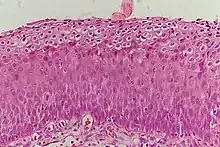

_normal_squamous_epithelium.jpg.webp)

Historically, abnormal changes of cervical epithelial cells were described as mild, moderate, or severe epithelial dysplasia. In 1988 the National Cancer Institute developed "The Bethesda System for Reporting Cervical/Vaginal Cytologic Diagnoses".[12] This system provides a uniform way to describe abnormal epithelial cells and determine specimen quality, thus providing clear guidance for clinical management. These abnormalities were classified as squamous or glandular and then further classified by the stage of dysplasia: atypical cells, mild, moderate, severe, and carcinoma.[13]

CIN is classified in grades:[14]

| Histology Grade | Corresponding Cytology | Description | Image |

|---|---|---|---|

| CIN 1 (Grade I) | Low-grade squamous intraepithelial lesion (LSIL) |

|